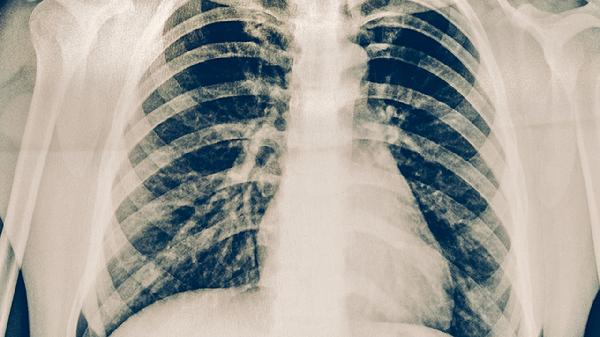

2.传统检查存在局限性

常规胸片对微小病灶识别度有限,就像隔着毛玻璃看风景。而低剂量螺旋CT能清晰显示毫米级结节,这种检测方式辐射量仅相当于乘坐两小时飞机。